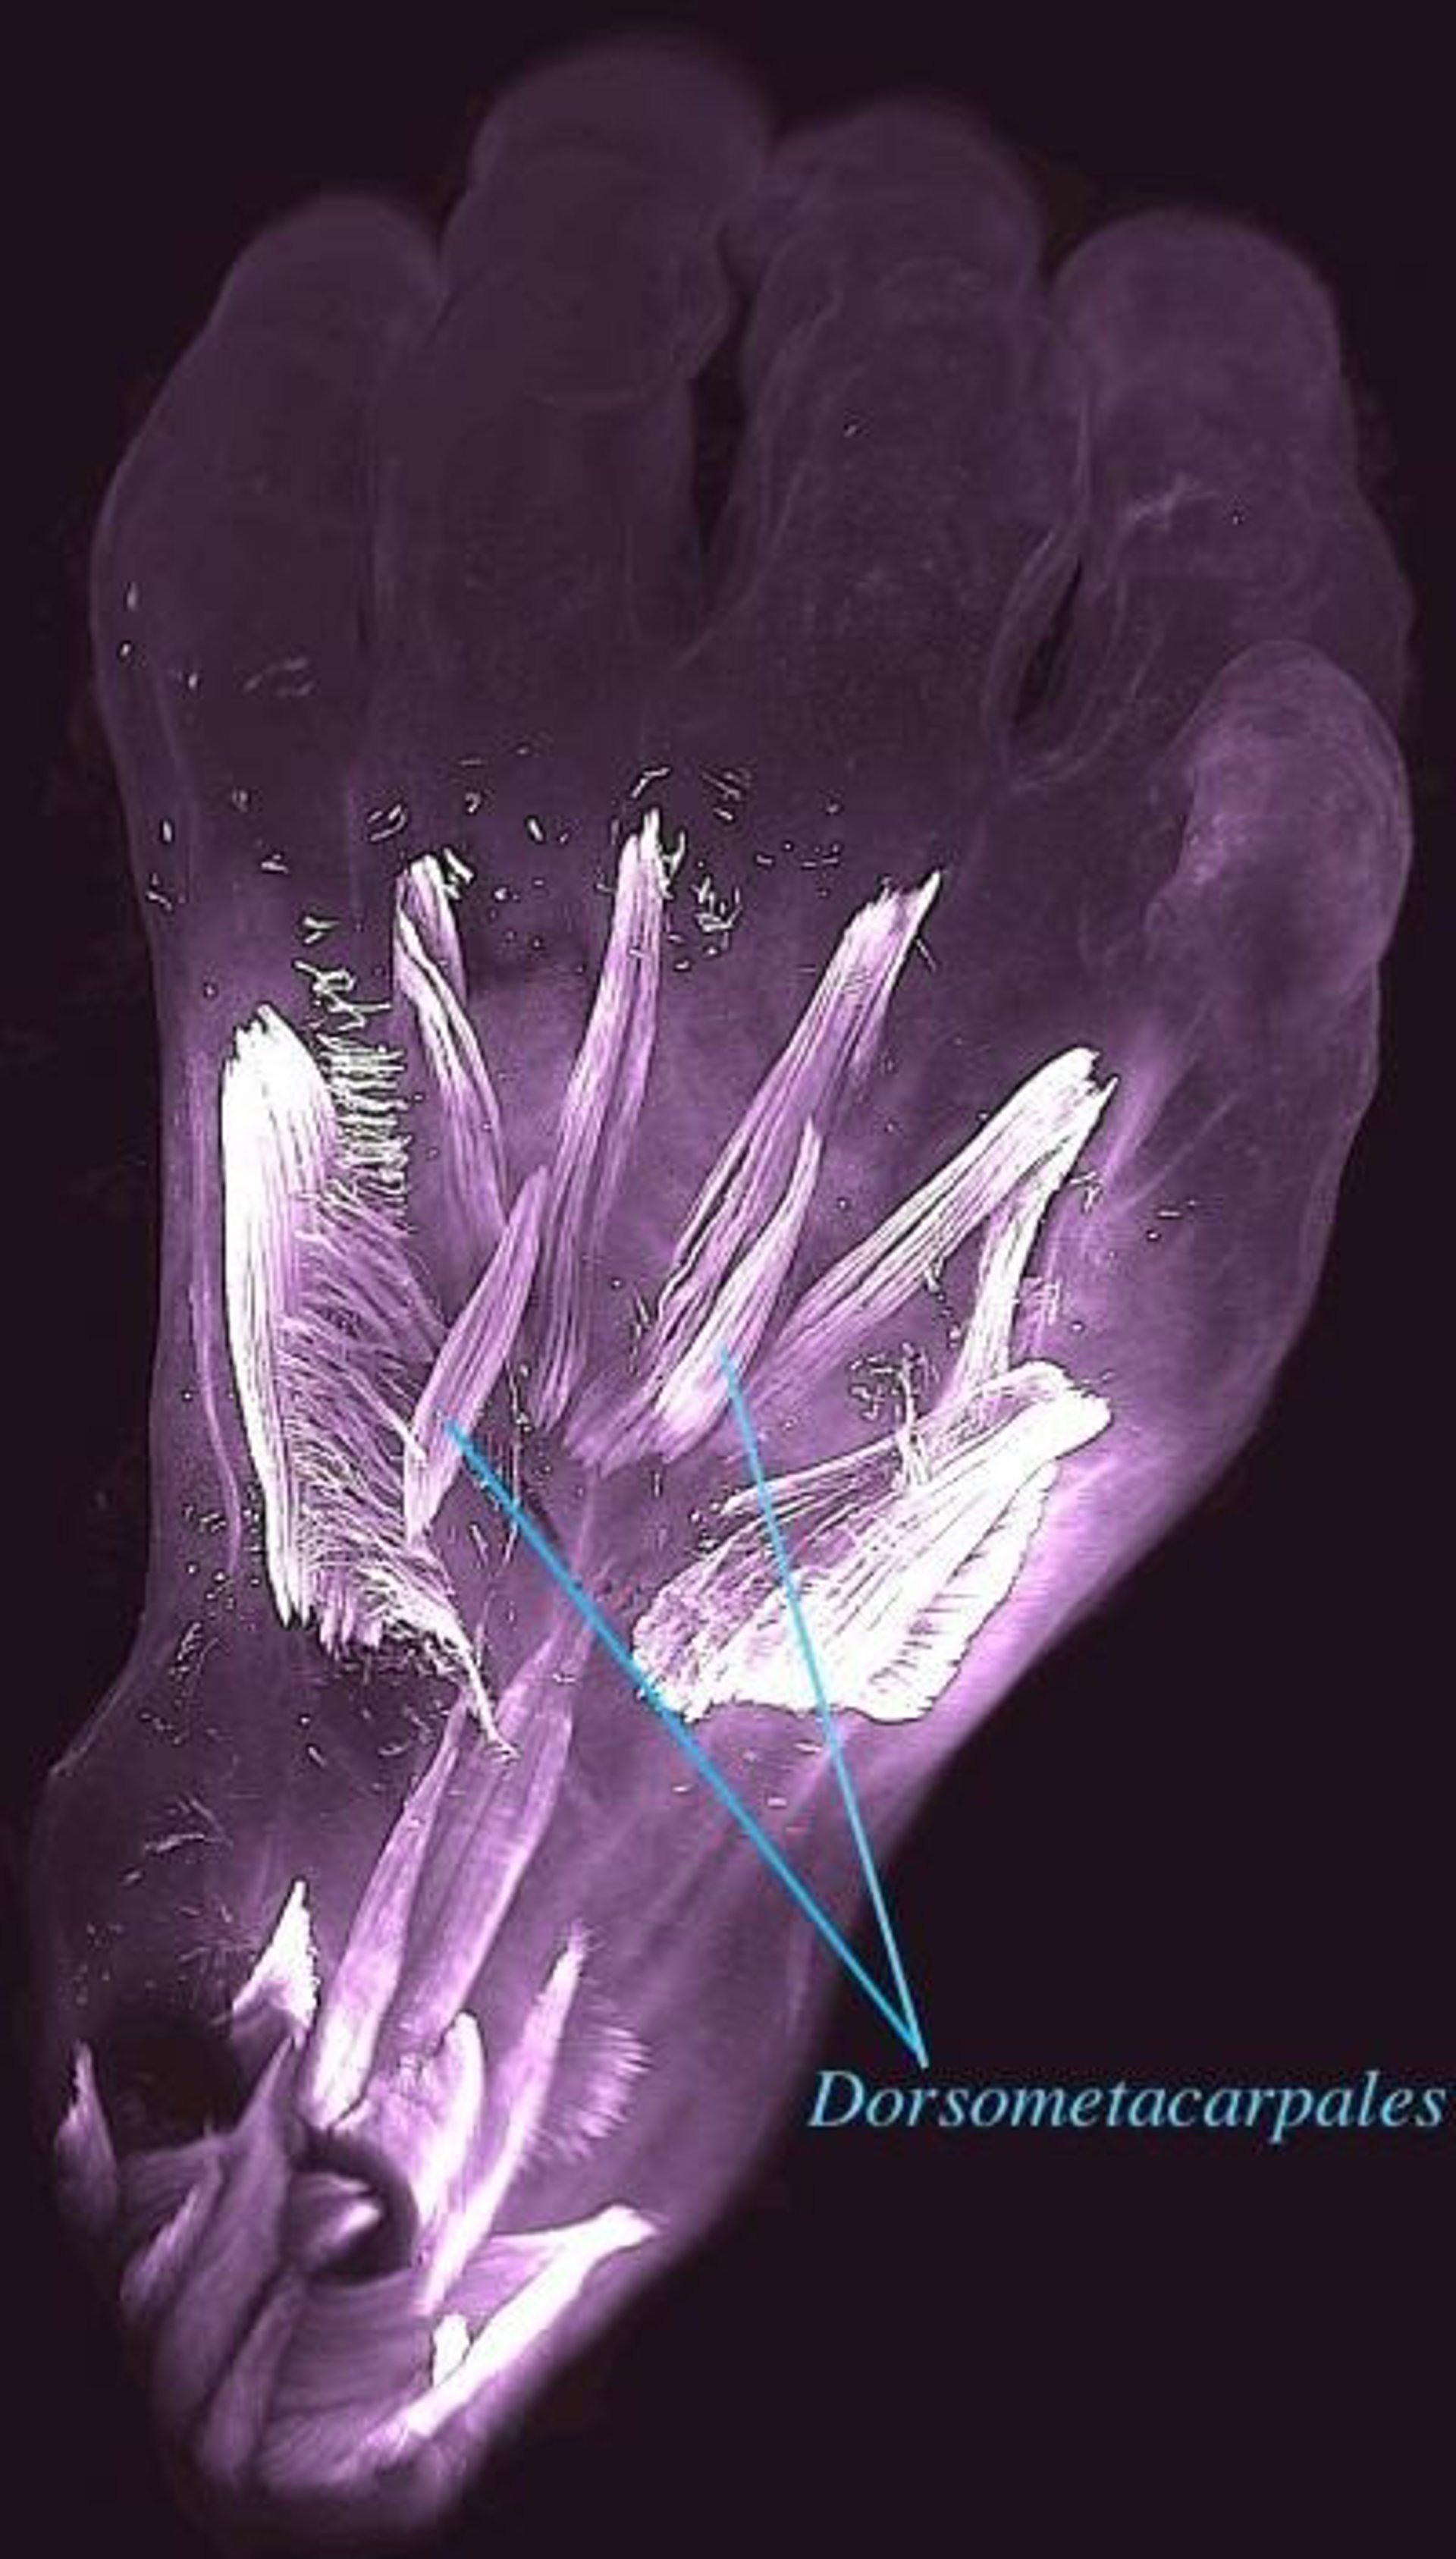

Vista dorsal de la mano izquierda de un embrión humano de 10 semanas de edad. Se destacan los dorsometacarpales

Vista dorsal de la mano izquierda de un embrión humano de 10 semanas de edad. Se destacan los dorsometacarpales - RUI DIOGO, NATALIA SIOMAVA Y YORICK GITTON

Según publican en la revista 'Development', sorprendentemente, algunos de estos músculos, como los dorsometacarpales, desaparecieron de nuestros antepasados adultos hace más de 250 millones de años, durante la transición de reptiles sinápsidos a mamíferos.